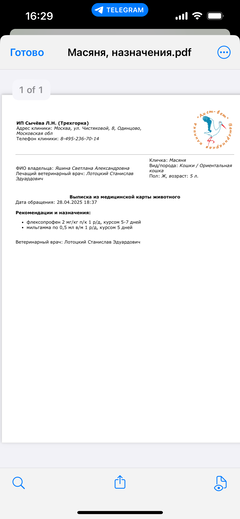

Ярко выраженная болезненность в области крестца, на обезболе полегче. По результатам приема невролога проведена миелография - множественная компрессия, возможно опухоль, возможно грыжа, нужно удалять...